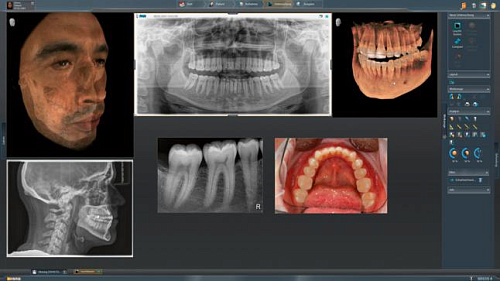

ORTHOPHOS SL 3D – это полный спектр обследований рентгенологии для стоматологической клиники любого уровня. Помимо получения снимков HD качества, важным моментом являются дополнительные пути для развития, которые появляются вместе с интеграцией в рабочий процесс Sirona.

Интегрированная имплантология с GALILEOS Implant

Все манипуляции, связанные с операциями имплантологического плана эффективны и безопасны. Для того чтобы наиболее оптимальным способом спланировать лечение, есть возможность совмещения цифровых слепков и рентгеновских изображений и объединения данных SIDEXIS 4 и CEREC 44.

Модернизированный сенсорный экран Easypad с понятным и удобным интерфейсом позволяет выставить наилучшие параметры контрастности и разрешения. Систематизация данных по диагностике становится значительно удобнее и проще с ПО обработки изображений SIDEXIS 4, ORTHOPHOS.

1. Двух-и трёхмерные снимки совмещаются в одной программе

2. В одном окне можно сравнивать разные 3D-результаты

3. Считанные минуты уходят на просмотр анамнеза пациента.

Временная шкала Timeline – это мгновенное получение информации полного спектра проведённых обследований пациента в порядке хронологии. В результате – экономия рабочего времени и повышение качества работы в целом.